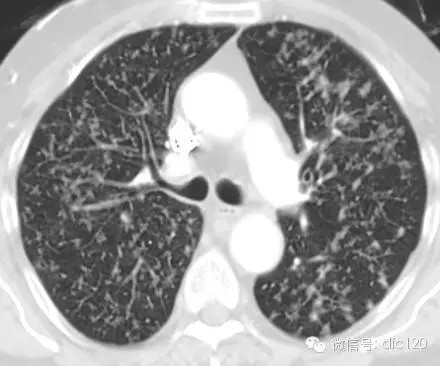

树芽征是指病变累及细支气管时,由于炎性渗出物或分泌物堵塞细支气管, CT表现为小叶中心分枝状线影和与其相连的细支气管横断面结节影,状如春天里挂满枝芽的”树”,即”树芽征”。是细支气管扩张、阻塞的特征影像之一。由Im等1993年首次报道,最初用来描述肺结核沿终末支气管扩散的征象,后来逐渐用于有类似征象的其它支气管疾病。CT尤其是高分辨CT(HRCT)能够很好的显示此征。

CT表现——在肺外围支气管的末梢呈现2~4mm大小结节与树枝状的高明电影。

意义:表明有小气道病变如:细支气管炎症、弥漫型细支气管炎级肺结核活动病灶或播散病灶等。